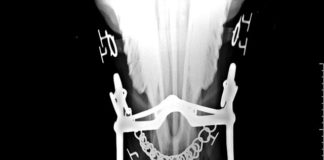

Fotoreportage: Die Heilung eines Pferdes mit Hufrehe und Hufbeindurchbruch

Eschweiler, Deutschland (Weltexpress). Alexandra Wilhelm, geboren 1977 in Aachen, führt als Diplombiologin in Eschweiler bei Aachen die Praxis für ganzheitliche Pferdegesundheit, deren Schwerpunkt auf...